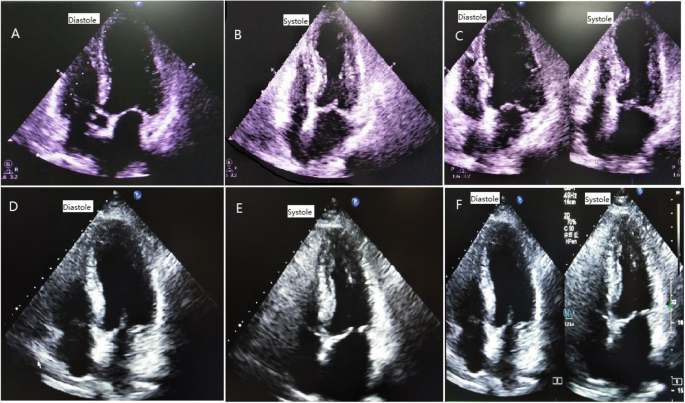

Cardiac examination at admission showed elevated repeated brain natriuretic peptide precursor (Pro-BNP), C-reactive peptide (CRP), high sensitivity C-reactive peptide (hs-CRP) and troponin T (cTnT) levels (Table 2). ECG revealed T-wave inversion on the inferior and anterior walls and an extended QT interval (QT/QTc 780/762 ms) (Fig. 3 a). Emergency bedside TTE showed left ventricular ballooning, apical dyskinesia, and abnormal diastolic function (LVEF being 36% by Simpson’s method) (Fig. 4 a b c), which was considered Takotsubo cardiomyopathy. Coronary angiography (CAG) performed 2 days later found no significant coronary arterial stenosis (Fig. 5), but left ventricular angiogram demonstrated the typical apical LV wall motion abnormalities and a peculiarly shaped LV (a round bottom and narrow neck), resembling the type of bottle used in Japan for trapping octopus (Figs. 6). Therefore, the patient was diagnosed with Takotsubo cardiomyopathy and treated with angiotensin converting enzyme inhibitor (ACEI), β-blocker and L-carnitine.

a b c Four-chamber view of TTE at admission showing ventricular “ballooning” caused by apical dyskinesis. d Four-chamber view of TTE at 7 days after treatment showing that LV apical “ballooning” was recovered. e f Four-chamber view of TTE two months later, showing no LV apical “ballooning” or wall motion abnormalities

At 10 days after treatment, Pro-BNP and cTnT levels were reduced to 500.8 pg/mL and 0.01 ng/mL, respectively (Table 1). ECG revealed that the T-wave inversion partially recovered, and the QT interval returned to normal, with QT/QTc being 440/350 ms (Fig. 3b). TTE showed recovered LV apical ballooning and normal wall motion at 10 days after treatment (Fig. 4 d).

At 2 months after treatment, there were no left ventricular apical ballooning or wall motion abnormalities, with LVEF at 63% by Simpson’s method (Figs. 4e and f).